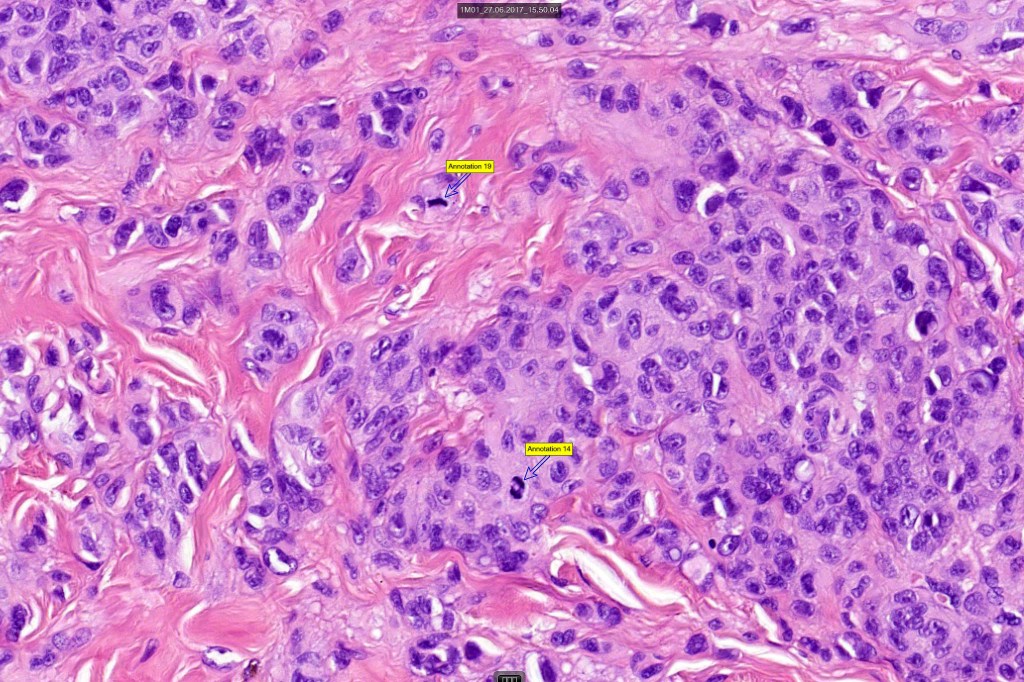

•Verrucous or dome-shaped, at low power, the lesion looks like a nevus

•Expansile nodules or diffuse

•Compression of connective tissue

•Subtle or not so subtle impaired maturation with depth (sometimes this is evident at scanning magnification)

•Subtle nucleolar prominence

•Subtle pleomorphism

•Mitoses invariable including often in the deep aspect

•S100 & SOX10 are useful to highlight impaired maturation